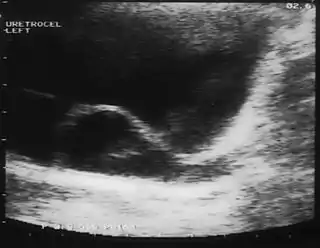

Ureterocele

El ureterocele es la dilatación quística del uréter distal intravesical (dentro de la vejiga urinaria).

El diagnóstico puede establecerse por ecografía de todo el tracto urinario (técnica de diagnóstico por imágenes que utiliza ondas de sonido de alta frecuencia, que tras atravesar tejidos de diferente densidad, son computabilizadas, dando una imagen de los vasos sanguíneos, tejidos, órganos internos, colecciones de líquido, masas, etc.). En ocasiones debe realizarse una pielografía endovenosa (PEV) que es una técnica diagnóstica radiológica en la que se administra un contraste endovenoso, que durante su excreción por la vía urinaria permite visualizar mediante radiografías seriadas, la velocidad y trayectoria del flujo urinario. También permite detectar alteraciones morfológicas congénitas (duplicidad pielocalicilar) o patológicas (hidronefrosis, obstrucciones intrínsecas y extrínsecas, etc.). UROGRAMA ESCRETOR,CISTOURETEROGRAFIA MICCIONAL EN PACIENTES ADULTOS